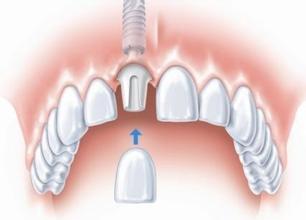

3、种植牙

种植牙首先是将种植体(即人工牙根)植入缺牙部位的牙槽骨内,一段时间后,再在种植体的上部完成固定或活动假牙修复。它除了具备固定假牙外,还不需磨除缺隙相邻的天然牙牙体组织。扩大了固定假牙的适应证。>>>了解三种假牙的费用,点击咨询

(种植假牙)

种植牙

优点:种植牙在形式与功能上近似于天然牙,符合正常生理要求;具有独立的人工牙根,无需磨损、不损伤相邻真牙;能更大限度地恢复咀嚼功能;能有效防止牙齿缺失后牙槽骨继续萎缩;稳固性较佳;美观效果逼真;能够解决传统镶牙方法无法解决的难题。

缺点:对全身健康和口腔健康要求较高,疗程较长,费用也高。

(种植牙修复效果)